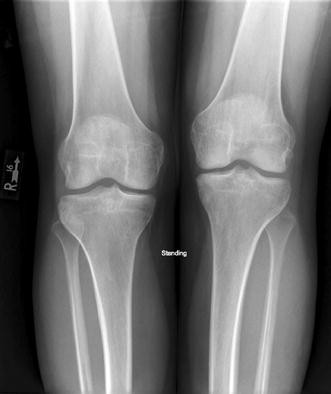

Chronic bilateral leg pain. Most leg pain results from wear and tear overuse or injuries in joints or bones or in muscles ligaments tendons or other soft tissues. Radiculopathy describes a range of symptoms produced by the pinching of a nerve root in the spinal column. I have suffered from chronic back of leghamstring pain for 10 years.

Chronic Facet Mediated Low Back Pain Chronic Pelvic Pain Inflammation. With this the symptoms and pain are experienced in both hips buttocks and legs at the same time. Bilateral calf chronic compartment syndrome is a rare cause of bilateral calf pain.